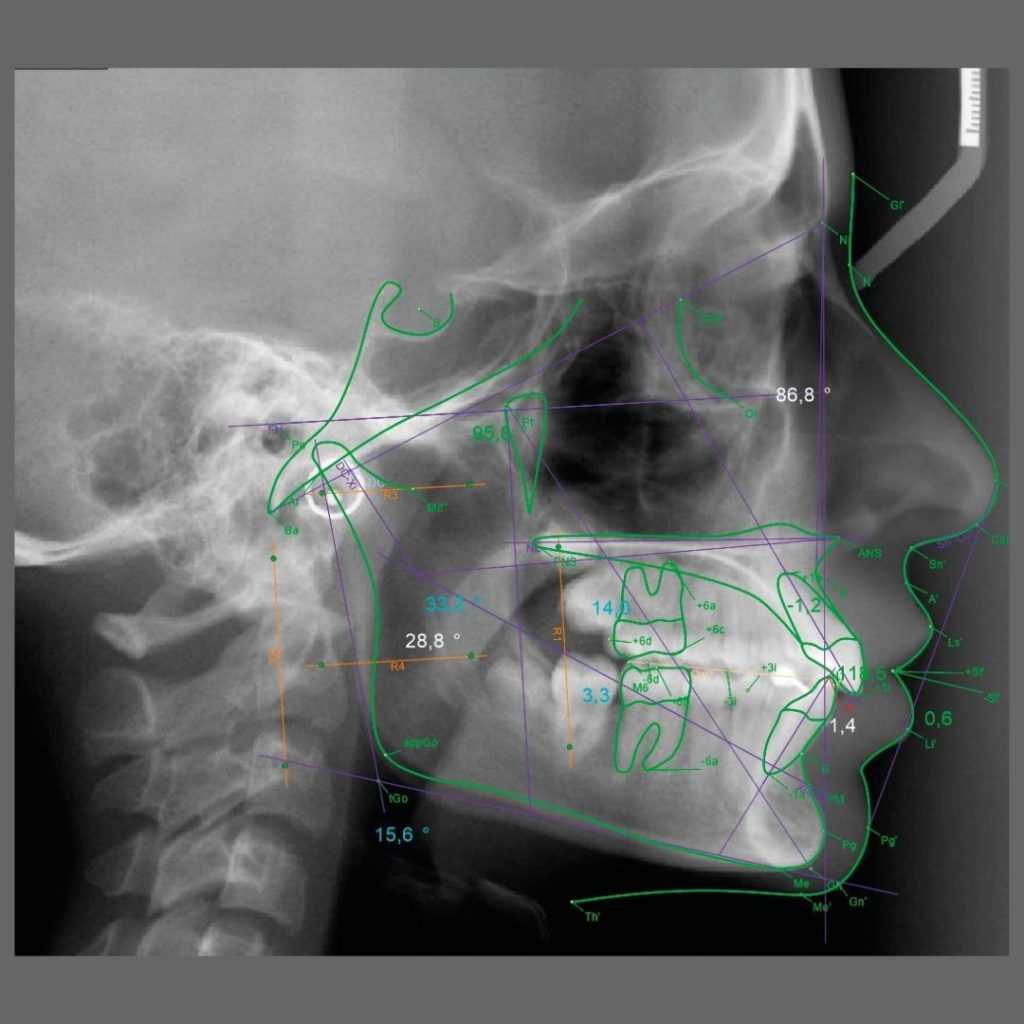

Trazados cefalométricos y fotografías clínicas de alta precisión.

Complementamos los estudios radiográficos con herramientas clave para la planificación ortodóncica y el seguimiento clínico. Realizamos trazados cefalométricos computarizados según múltiples métodos reconocidos y fotografías clínicas estandarizadas para una documentación completa del paciente.

- Trazado cefalométrico (Ricketts, McNamara, Gianni-Pistoni, Bjork-Jarabak, Harvold, Steiner, Tweed, Schwarz, entre otros).